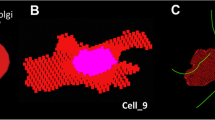

Four types of liposomes were prepared having membranes with different combinations of release (R) and adhesion (A) properties. The combinations were R−A−, R−A+, R+A−, and R+A+. These afford different penetrating properties into tissue. The liposomes were loaded with either carboxyfluorescein diacetate succinimidyl ester (CFDA-SE) or 225Ac. MDA-MB-231 spheroids were treated with the CFDA-SE-liposomes, harvested at different times, and the time-integrated CFDA-SE concentration at each radial position within the spheroid was determined. This was translated into mean 225Ac decays/cell versus radial position, uploaded to MIRDcell, and the surviving fraction of cells in spherical multicellular clusters was simulated. The MIRDcell-predicted surviving fractions were compared with experimental fractional-outgrowths of the spheroids following treatment with 225Ac-liposomes.

Katugampola S, Wang J, Howell RW. MIRD Pamphlet No. 27: MIRDcell V3, a revised software tool for multicellular dosimetry and bioeffect modeling. J Nucl Med. 2022. https://doi.org/10.2967/jnumed.121.263253.